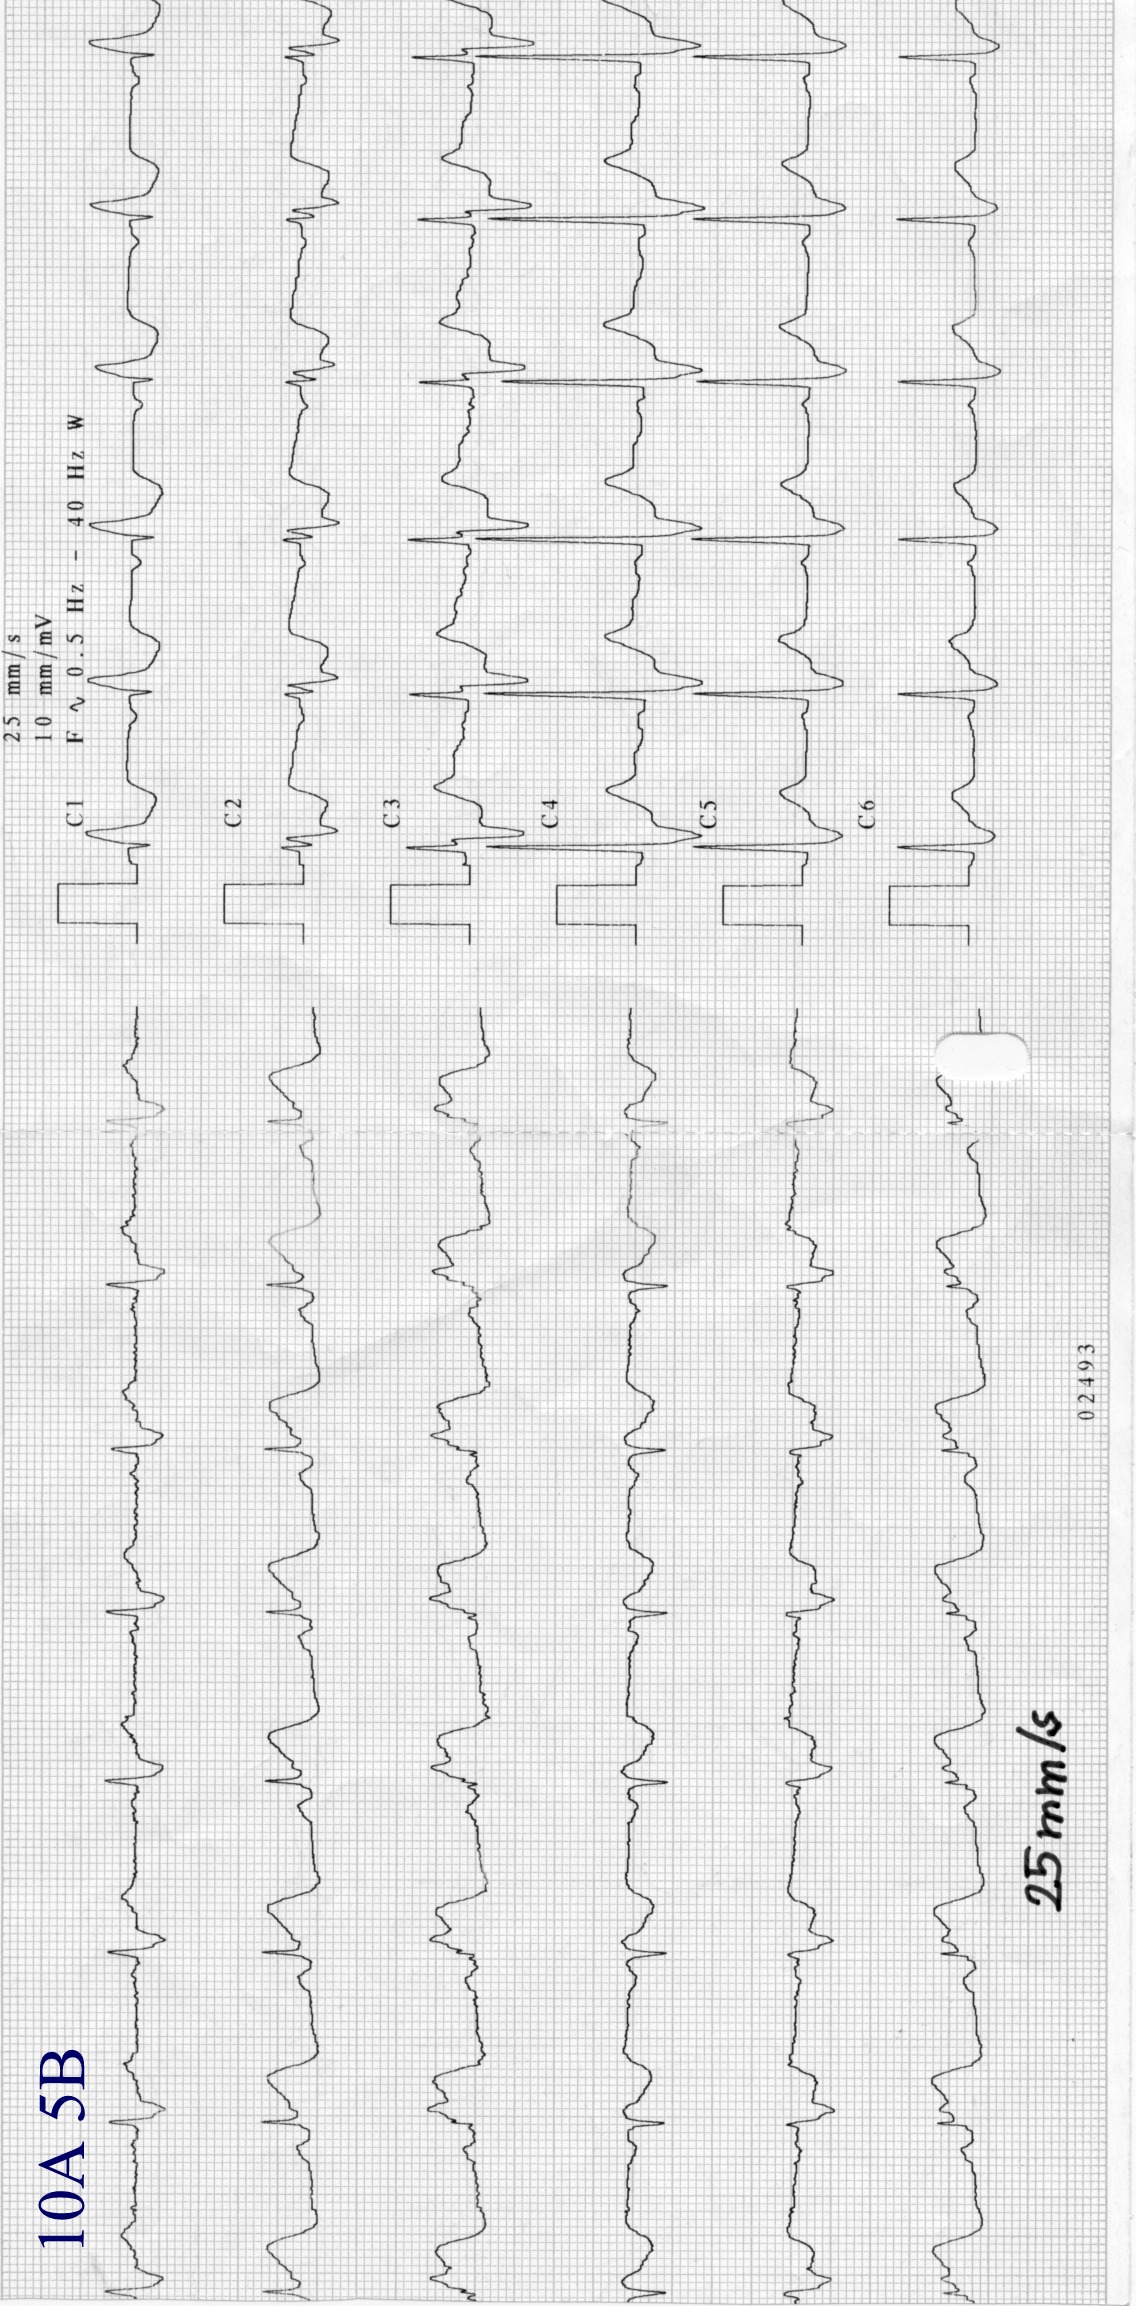

Zapis 10